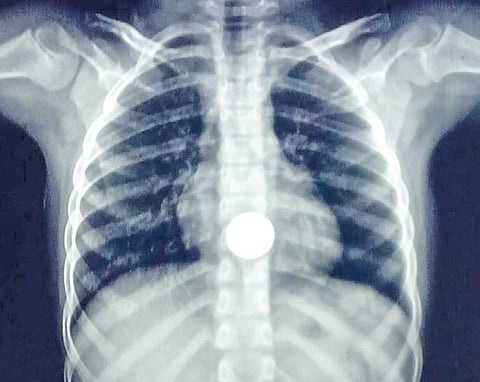

According to a release, the girl, who was initially taken to the Musiri government hospital, was referred to MGMGH due to the “critical nature” of her condition. On examination and after X-ray diagnosis, the doctors there discovered that the coin was lodged in her upper esophagus and was not passing.